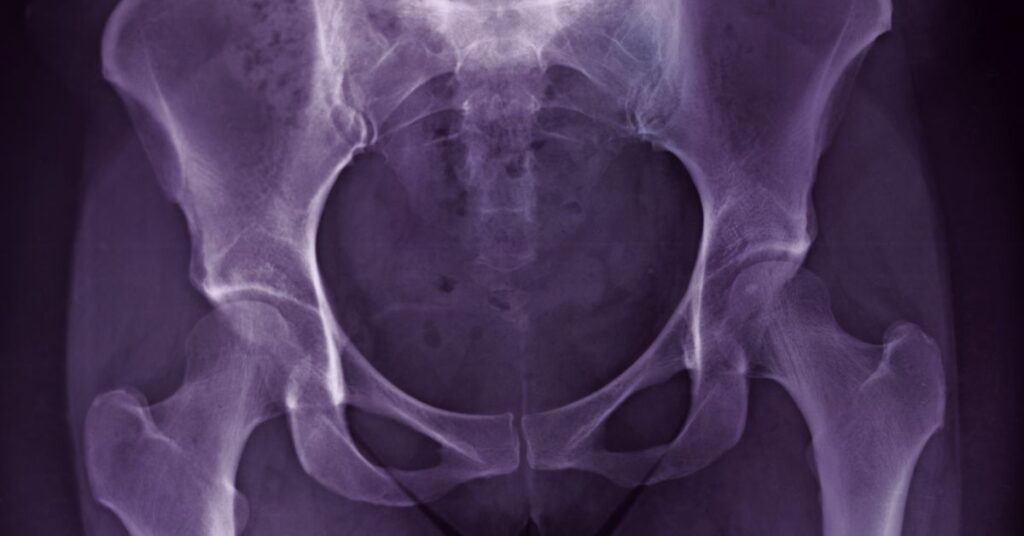

Do you feel a deep ache in your groin or stiffness in your hip when walking or getting out of a chair? You may be one of millions dealing with…

Do you feel a sharp pain deep in your groin or front of your hip? Does your hip click, catch, or feel unstable—especially when sitting, squatting, or twisting? You might…